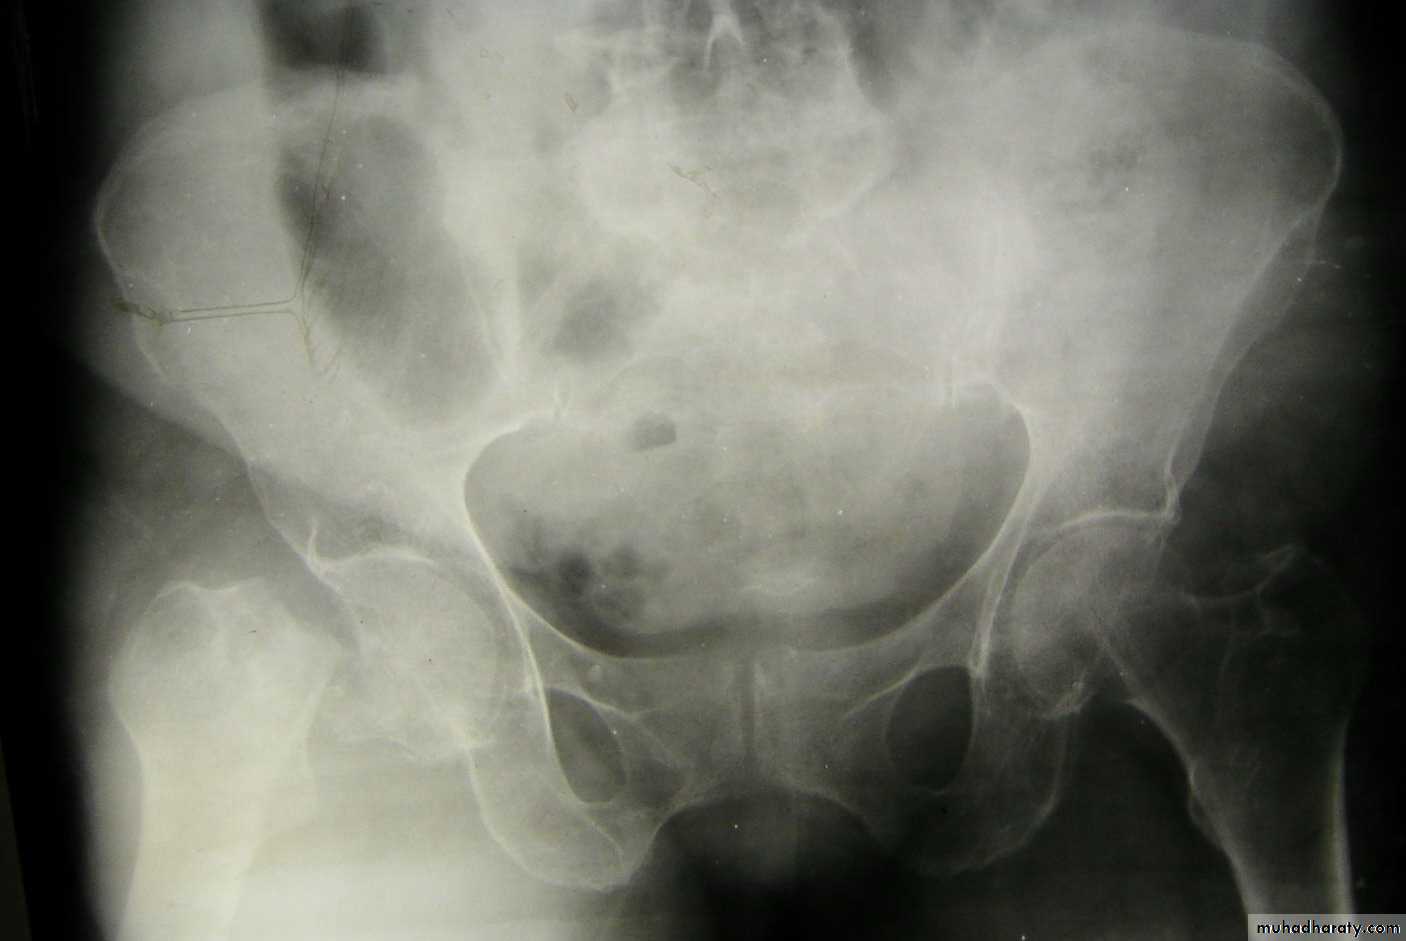

Central fracture -dislocation

Lower limbs